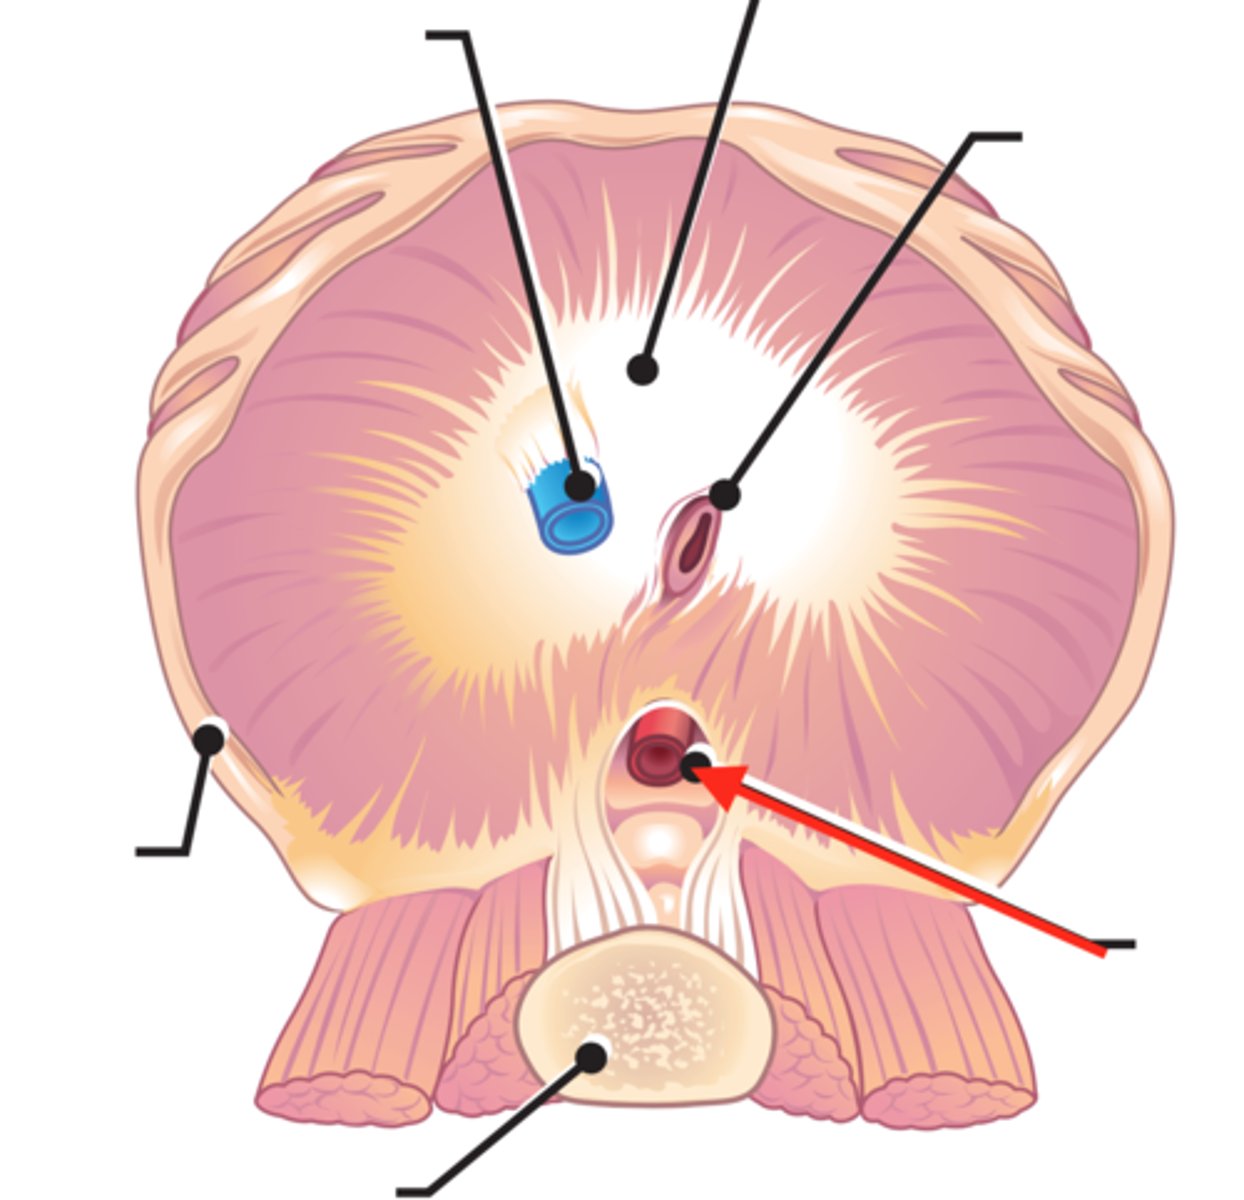

thoracic diaphragm

caval foramen

carries the inferior vena cava from the abdomen to the thorax to empty blood into the right atrium of the heart

Oesophageal hiatus

allows the oesophagus to enter the abdomen to empty food into the stomach

aortic hiatus

opening in diaphragm for the aorta to pass from the heart to the abdomen